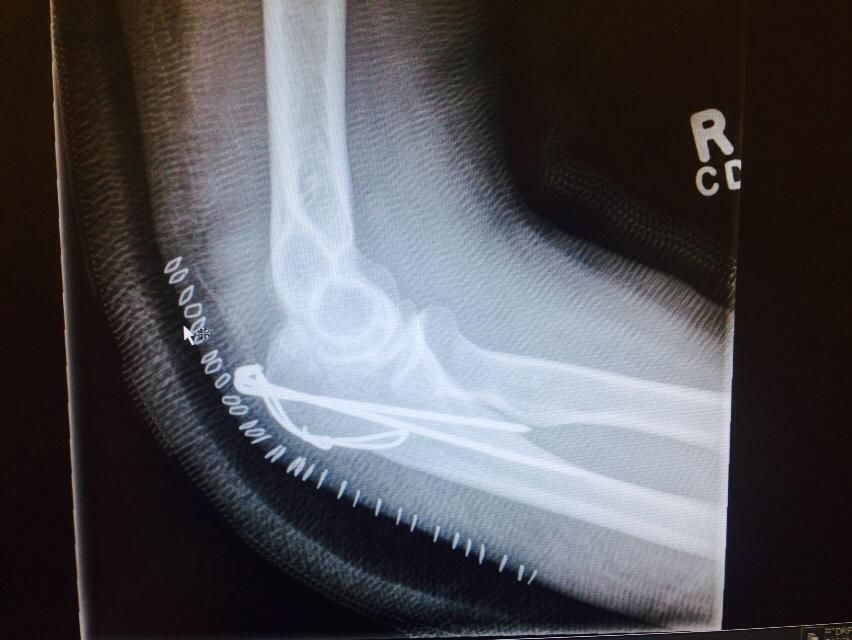

This past Thursday I got all of the staples out and the cast off. I was also able to get an idea of what they’d done, which was put in a couple of pins and some wire to hold it all together. I still have a wicked bruise and will for a few weeks before it gets absorbed back in. It’s really hard where the bruises are and I seem to have lost a lot of feeling on the back of my arm. Hopefully that comes back!

Loved the pictures. The Xray was great for seeing what actually happened.